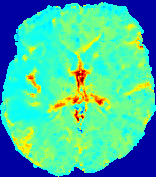

LesionRefer to captionRefer to captionRefer to captionRefer to captionRefer to captionRefer to caption𝐕rgbsubscript𝐕𝑟𝑔𝑏{\bf{V}}_{rgb}Refer to captionRefer to captionRefer to captionRefer to captionRefer to captionRefer to caption𝐕2subscriptnorm𝐕2{\|\bf{V}}\|_{2}Refer to captionRefer to captionRefer to captionRefer to captionRefer to captionRefer to captionRefer to caption3.53.53.52.82.82.82.12.12.11.41.41.40.70.70.70.00.00.0(mm/s)𝑚𝑚𝑠(mm/s)D𝐷DRefer to captionRefer to captionRefer to captionRefer to captionRefer to captionRefer to captionRefer to caption0.0200.0200.0200.0160.0160.0160.0120.0120.0120.0080.0080.0080.0040.0040.0040.0000.0000.000(mm2/s)𝑚superscript𝑚2𝑠(mm^{2}/s)Slice #1Slice #2Slice #3Slice #4Slice #5Slice #6

Figure 3: PIANO feature maps for one stroke patient, where the lesion is located in the left hemisphere. Top row: segmented stroke lesion region (white) on different slices, obtained from ISLES 2017. The corresponding slices for the PIANO feature maps are shown in the following rows.

For a better insight into an estimated velocity field 𝐕𝐕{\bf{V}} and diffusion field 𝐃𝐃{\bf{D}}, we compute the following maps: (1) 𝐕rgbsubscript𝐕𝑟𝑔𝑏{\bf{V}}_{rgb}: Color-coded orientation map of 𝐕=(Vx,Vy,Vz)T𝐕superscriptsuperscript𝑉𝑥superscript𝑉𝑦superscript𝑉𝑧𝑇{\bf{V}}=(V^{x},V^{y},V^{z})^{T}, obtained by normalizing 𝐕𝐕{\bf{V}} to unit length and mapping its 3 components to red, green, blue respectively; (2) 𝐕2subscriptnorm𝐕2\|{\bf{V}}\|_{2}: 222 norm of 𝐕𝐕{\bf{V}}; (3) D𝐷D: scalar field in Eq. 5.

Fig. 3 and Fig. 4 show the PIANO feature maps estimated from two ISLES 2017 patients: all are highly consistent with the lesion in both cases. Details of the blood flow trajectories are revealed in 𝐕rgbsubscript𝐕𝑟𝑔𝑏{\bf{V}}_{rgb} by the ridged patterns and the sharp changes of colors in the unaffected (right) hemisphere, while the flat patterns appearing within the lesion provide little directional information about the velocity and indicate low velocity magnitudes. Velocity magnitudes are more directly visualized via 𝐕2subscriptnorm𝐕2\|{\bf{V}}\|_{2}, from which one can easily locate the lesion where 𝐕2subscriptnorm𝐕2\|{\bf{V}}\|_{2} is low. D𝐷D also indicates lower diffusion values in the lesion, though with less contrast potentially due to the fact that it captures the accumulated effect of CA diffusion at the voxel-level.